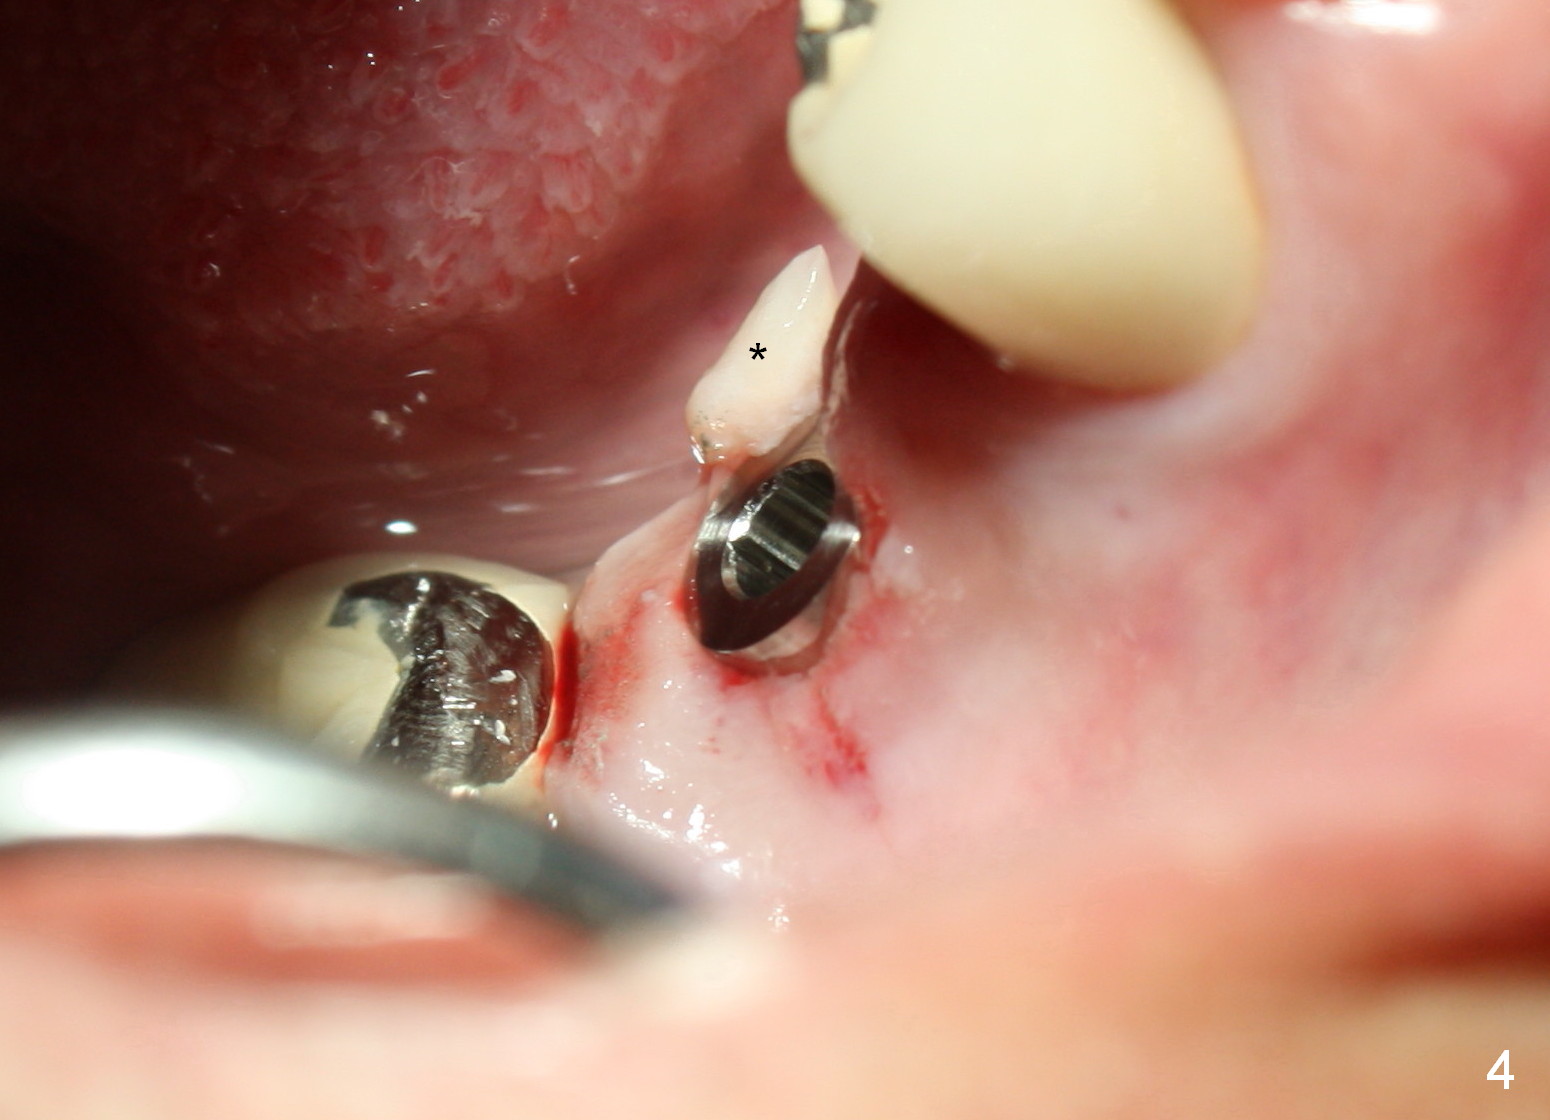

A 47-year-old man has history of bruxism, chipping porcelain from #29-31 FPD (Fig.1). Following sectioning the FPD, osteotomy is created (Fig.2: 5x14 mm drill) for placement of a 5x14 mm tissue-level implant (Fig.3,4). A 4x3 mm abutment (Fig.5 (lingual view) A) with 3 vertical slots (* for increased retention) is placed to retain periodontal dressing. The crown over the implant has dislodged 3 times over 28 months post cementation (Fig.6). It appears that the top of the abutment is too rounded. Clinical exam shows that the abutment height can be more, although the tooth #3 is supraerupted (Fig.7 (orthodontic intrusion is not indicated because of furca infection)).

Therefore a larger and longer abutment should be used (4.5x5 mm 0°). First of all, install Isolite. Remove cement from the access hole of the unipost with Cavitron. The cement was used to cement the crown. Use Tatum driver to remove the abutment. If it does not work, make a slot on the top of the abutment and use a regular screw driver to unscrew the abutment. Second, apply Cetacaine and perform laser gingivectomy to expose the implant margin. Temporary crown should be made to keep the margin and the space just created around the implant. Third try in the new abutment. Fourth reduce the abutment height carefully and make slopes corresponding the cusps of the opposing tooth. Reduce the opposing tooth if necessary. Last, consider Ketac cementation. Use resin bonding (with syringe tip) when an angled abutment is used. The bonding has higher retention than Ketac.

Pre-impression photos show supraerupted #3 (Fig.7). Clearance is a little more than 1 mm between the mesiopalatal cusp of #3 (Fig.7 *) and the rounded abutment (Fig.8). Removal of the abutment turns out to be easy. Reduction is confined to the opposing tooth (slopes of the cusps). No occlusal reduction is done for the new abutment as mentioned above except for 2 retention grooves. One-mm reduction ring barely passes the occlusal clearance (Fig.9). No cement is applied to the abutment in case a longer abutment may be required. Bone density seems to remain the same or increase after cementation of a new crown (Fig.7). The redo crown remains in place 1 year post cementation.